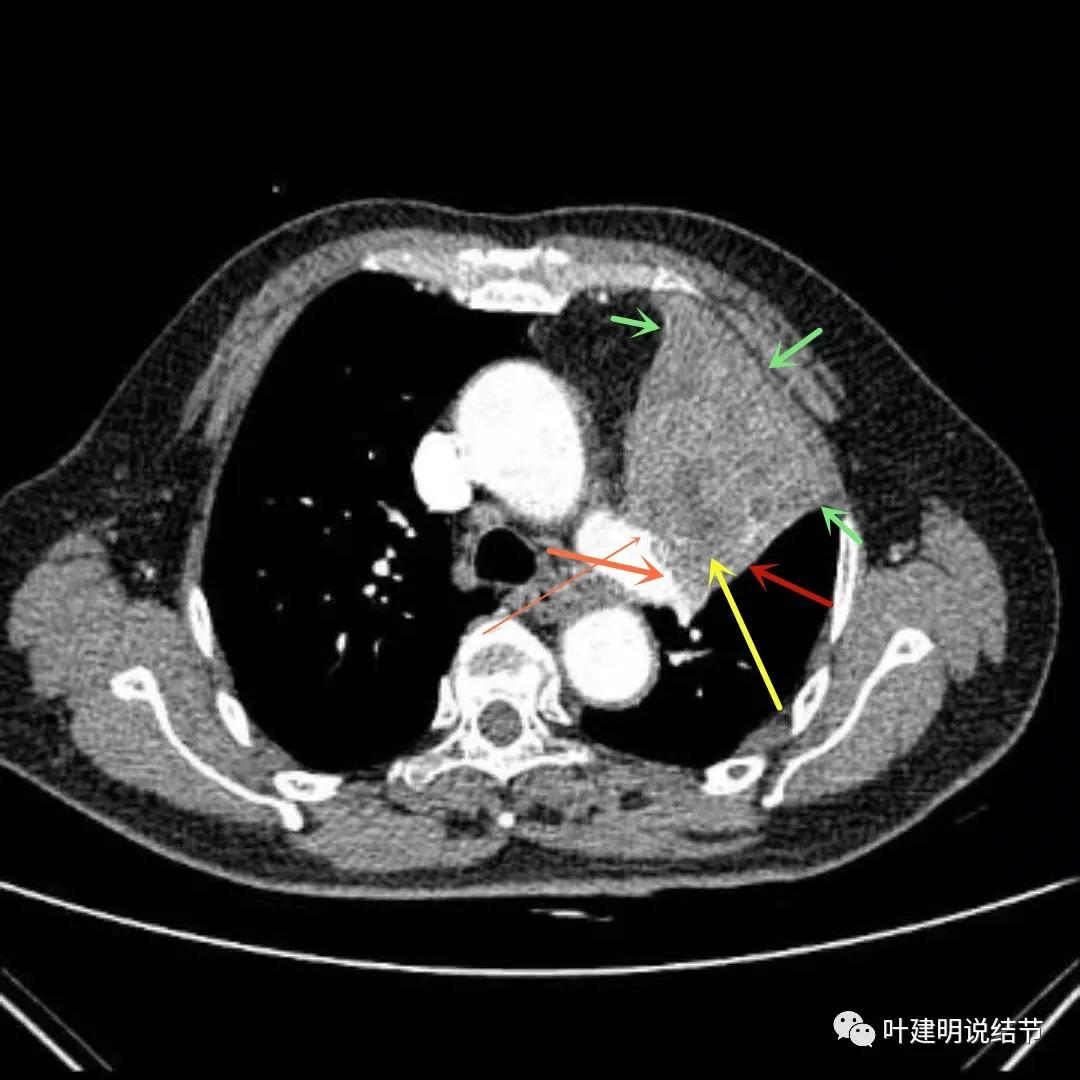

上图示左上肺肿块,边缘部分应该考虑是不张的肺组织,但黄色箭头所指处是肿瘤内部的坏死区

上图绿色箭头所指区域考虑不张的肺组织,红色箭头所指附近为肿瘤,且有膨胀性

上图绿色箭头所指区域考虑为肺不张,红色示肿瘤处,黄色箭头示肿瘤区域内有坏死低密度,桔色细箭头所指处是被肿瘤包绕的肺动脉分支起始部,粗桔色箭头示肺动脉与肿瘤间紧密愈着,考虑有侵犯肺动脉